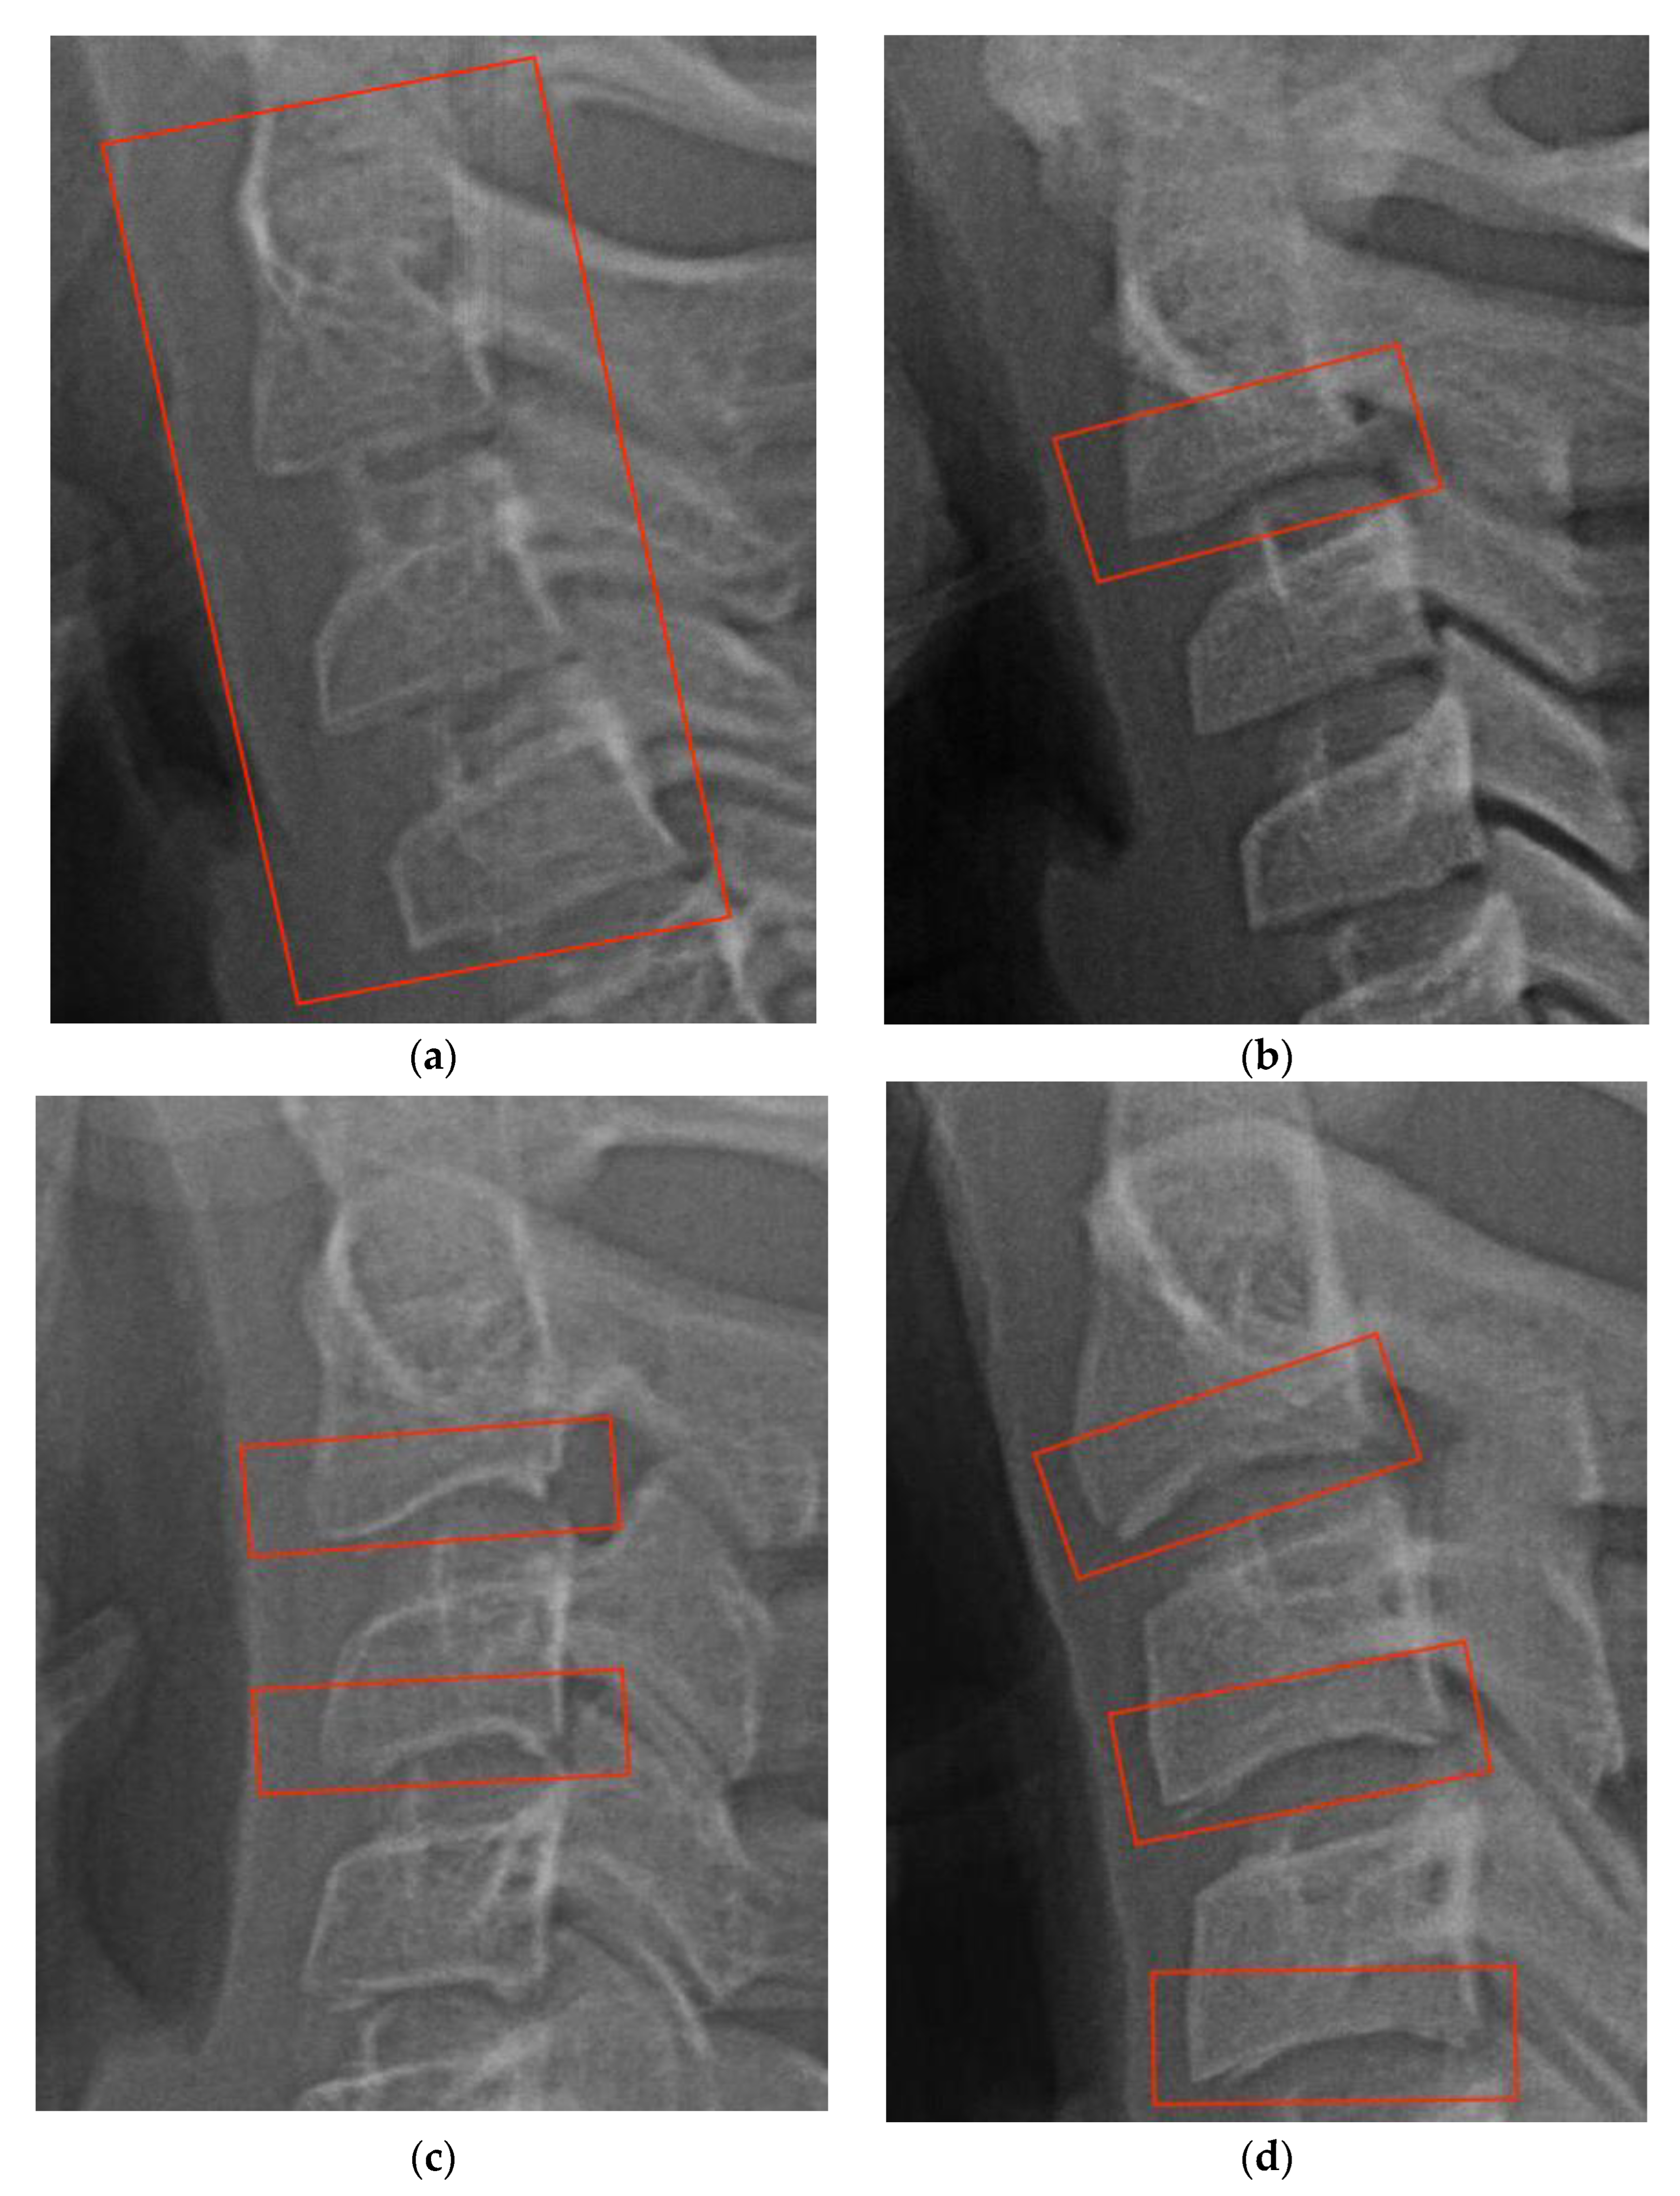

2. Cervical Vertebral Maturation Method

3.5. Dataset